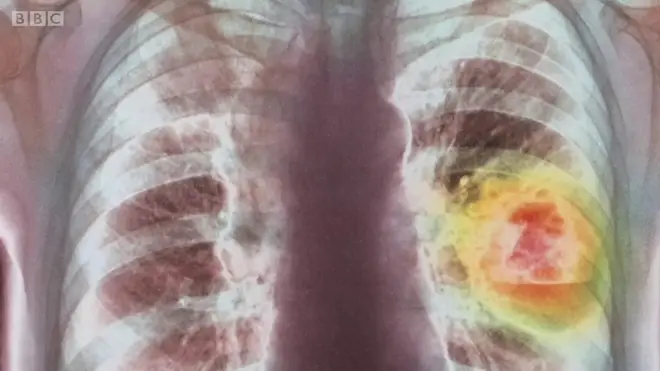

การงดอาหารประเภทแป้งและน้ำตาล หรือ "คีโตเจนิกไดเอ็ต" (Ketogenic diet) จะทำให้ร่างกายหันไปเผาผลาญพลังงานจากไขมันที่สะสมไว้ จนทำให้เกิดการผลิตสารคีโตนซึ่งช่วยป้องกันรักษาเซลล์สมองจากอนุมูลอิสระขึ้น นักวิจัยบางคณะกำลังทดลองใช้วิธีกินอาหารแบบนี้เพื่อรักษามะเร็งสมองด้วย